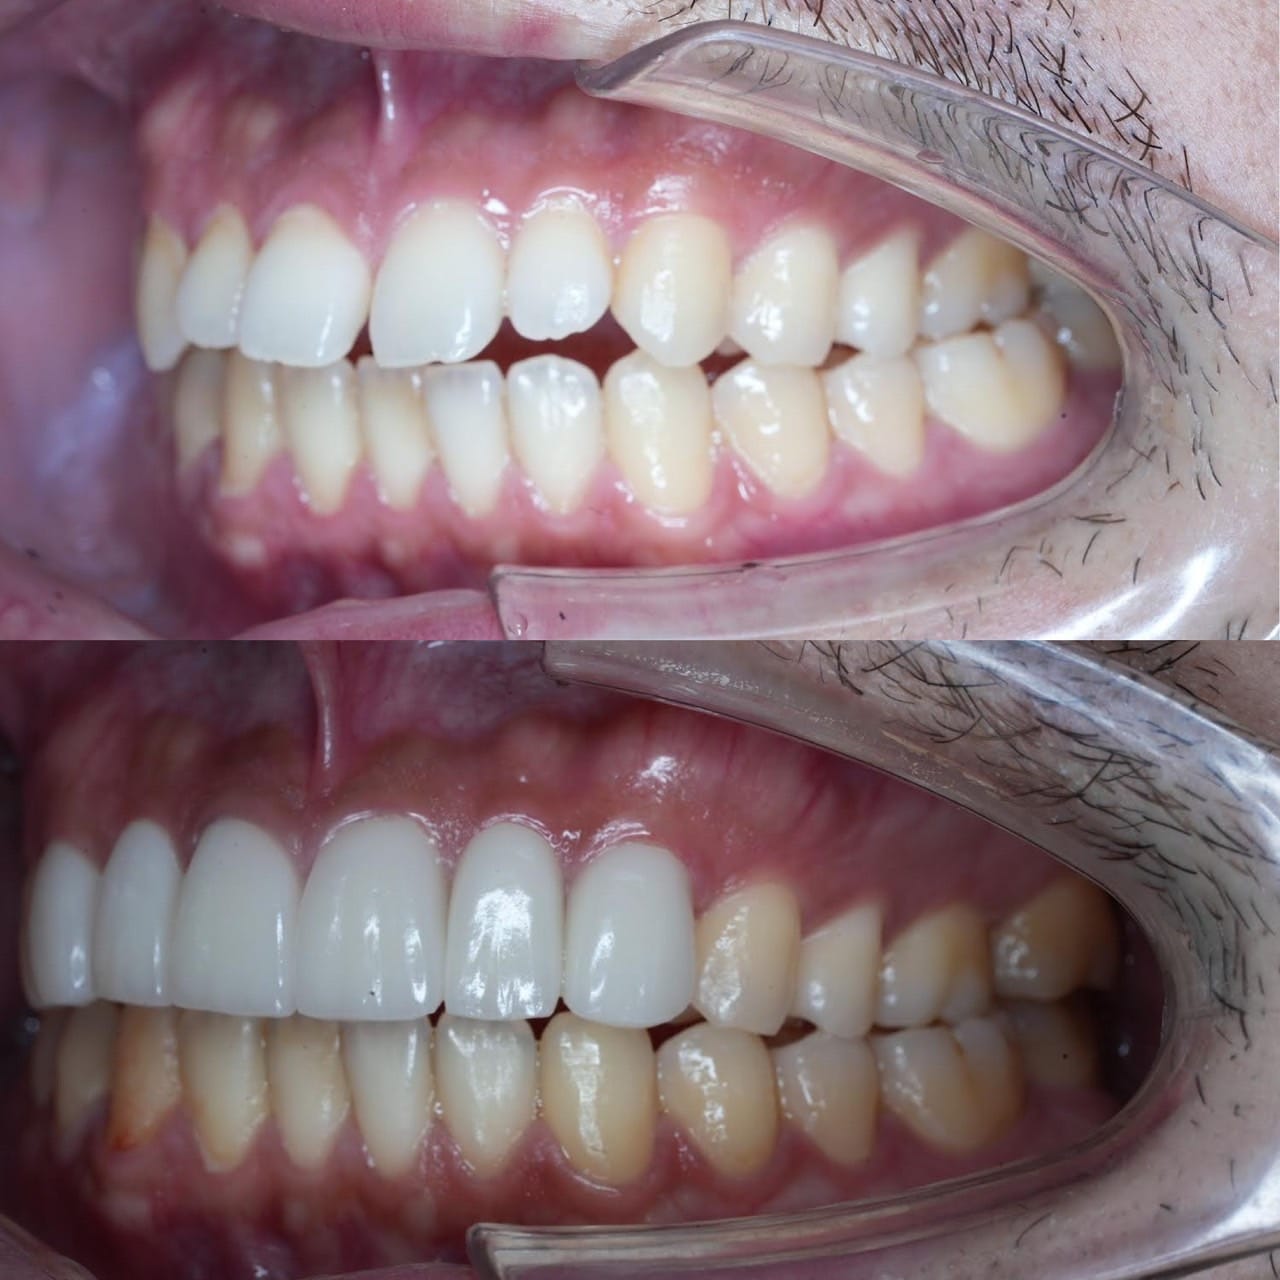

Case032

メジャーリーグでも活躍した元プロ野球選手の山口俊さんのセラミック治療を担当いたしました。

「他院で治療を受けたセラミックが欠けた」というのが主訴でしたが、よく診察するとセラミック欠けただけではなく、被せ物がしっかりと合っていないことが原因で歯茎の腫れがあり、歯石や汚れもつきやすい状態でした。また、歯列も若干歪んでいたので、この機会に全て治療いたしました。

治療後は透明感のある白さで、綺麗な歯並びになりました。また、セラミックをきちんと綺麗に削って適合よくセットしたことにより、歯茎の腫れも改善しました。

セラミックを入れた所の歯茎が腫れていて悩まれてる方はぜひご相談ください。

綺麗に削って適合よくセラミックをしてあげれば必ず改善します。